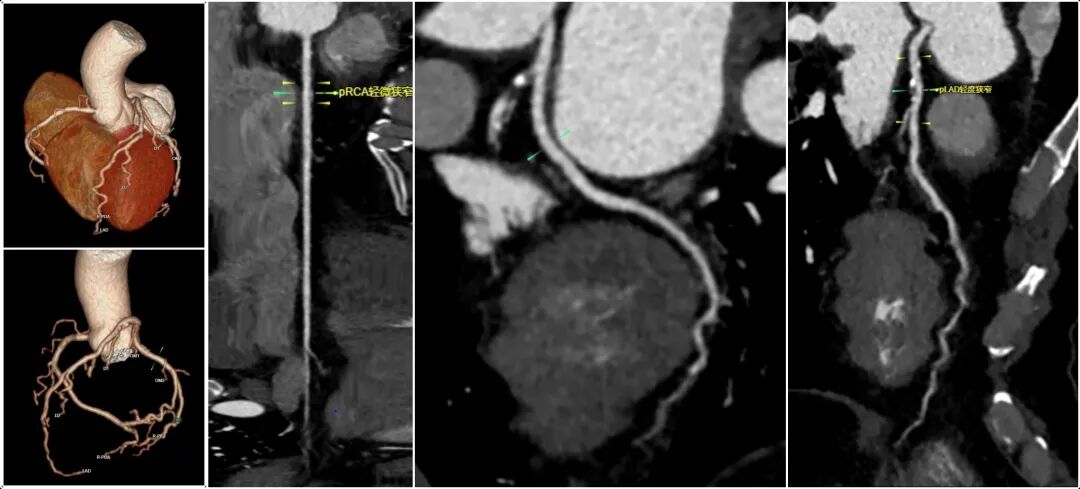

我院全新引进的GE256排512层Revolution CT机(“革命”CT)突破临床禁忌,面对所有CT冠脉成像的难点和禁区,可以实现一个心跳数据全心成像。

16厘米宽体探测器一次完整覆盖整个心脏,24毫秒业界最快心脏时间分辨率,可同步获取心脏各个层面的容积数据,保证容积数据在空间及相位的一致性。

一次心跳,不受心率、心律、呼吸运动等因素影响。

一次对比剂注射,在一次心跳内,可以同时获得冠脉解剖学信息、斑块成分信息、心脏4D运动信息、心功能信息和心肌灌注信息等,为后续的诊断和治疗提供更丰富的指导依据。

以最高效的方式解决复杂的冠脉成像难题,有效避免了传统CT检查容易受到心律不齐、呼吸运动、心脏搏动等因素影响,肺功能较差、心房颤动、心律不齐及老龄人可以不受限制地通过该设备完成检查。